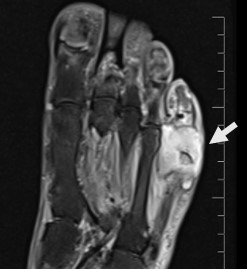

Case: A 65-year-old male patient with a history of kidney transplantation 10 years ago was admitted to outpatient clinic for erythema and edema on the dorsum of his left foot. He had no history of trauma. He was diagnosed with cellulitis due to leukocytosis and elevated CRP levels with his symptoms, and subsequently got oral antibiotic therapy. One week after the redness subsided, the discomfort intensified and CRP levels elevated further. Foot MRI has been performed and osteomyelitis in his fifth mettarsal bone has been investigated (figure 1). An MRI of the foot was conducted to evaluate osteomyelitis in the fifth metatarsal bone. Following a further 6 weeks of intravenous antibiotic treatment, a fistula developed, leading to a debridement surgery for sampling. Cryptococcus neoformans serotype A was isolated from bone tissue culture and treatment with fluconazole was initiated. A nodular lesion was observed in his chest CT scan despite the lack of respiratory symptoms (figure 2). There were no neurological symptoms or meningeal involvement observed in the cranial MRI, nevertheless, a lumbar puncture was conducted. A positive Cryptococcus neoformans latex agglutination test was detected in the cerebrospinal fluid analysis, requiring a change in his antifungal treatment to liposomal amphotericin B for disseminated disease involving central nervous system. During the same week, prostate imaging was conducted due to urinary retention, and an abscess was examined. Cryptococcus neoformans serotype A was cultured from the abscess after it was drained. Following a 4-week course of Liposomal amphotericin B treatment, antifungal medication was changed to fluconazole and continued for 12 months until full recovery and no complications or immune reconstitution inflammatory syndrome (IRIS) occurred, although a urinary tract infection developed during the therapy.